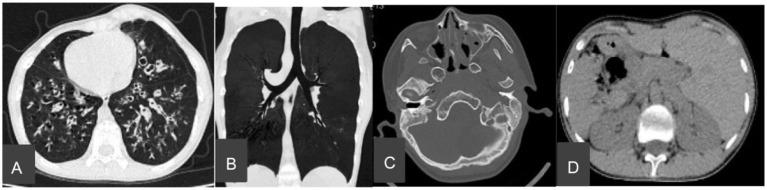

Kartagener syndrome (KS), a subtype of primary ciliary dyskinesia (PCD), is a rare genetic disorder characterized by , chronic sinusitis, bronchiectasis, recurrent respiratory infections, and impaired ciliary function. It is diagnosed through physical examination, imaging techniques such as computed tomography (CT), nasal nitric oxide measurement, genetic testing, and pulmonary function tests. We present a case study of a 15-year-and-11-month-old male patient with KS complicated by sinusitis, secretory otitis media, and bronchiectasis. The patient exhibited , affecting the lungs, heart, and abdominal organs. Treatment included antibiotics for infection, mucolytics, and pulmonary rehabilitation. Postural drainage and bronchoscopy were performed for lung lavage. Following treatment, the patient's respiratory symptoms improved, and lung function tests showed improvement. A literature review identified a high prevalence of lung and heart transpositions in Chinese patients with PCD, while abdominal organ transposition was less commonly reported. Genetic analysis revealed compound heterozygous mutations in the gene, specifically c.12279 + 1 G > A (exon 71, NM_001369) and c.9457 C > T (exon 56, NM_001369), including the newly discovered variant c.9457 C > T (exon 56, NM_001369). This novel mutation expands the genetic landscape associated with KS, providing further insights into the underlying genetic basis of the condition. The study emphasizes the clinical features, the limited reporting of abdominal organ transposition, the genetic basis, and the treatment of KS, thereby contributing to the understanding and management of this condition.

卡塔格内综合征(KS)是原发性纤毛运动障碍(PCD)的一种亚型,是一种罕见的遗传性疾病,其特征为慢性鼻窦炎、支气管扩张、反复呼吸道感染和纤毛功能受损。通过体格检查、计算机断层扫描(CT)等成像技术、鼻一氧化氮测量、基因检测和肺功能测试进行诊断。我们报告了一例15岁11个月大的男性KS患者,其并发鼻窦炎、分泌性中耳炎和支气管扩张。该患者表现出[此处原文缺失相关表现描述],影响肺部、心脏和腹部器官。治疗包括抗感染的抗生素、黏液溶解剂和肺康复治疗。进行体位引流和支气管镜检查以进行肺灌洗。治疗后,患者的呼吸道症状改善,肺功能测试显示有所改善。文献综述发现,中国PCD患者中心脏和肺换位的患病率较高,而腹部器官换位的报道较少。基因分析揭示了该基因中的复合杂合突变,具体为c.12279 +1 G>A(外显子71,NM_001369)和c.9457 C>T(外显子56,NM_001369),包括新发现的变异c.9457 C>T(外显子56,NM_001369)。这种新的突变扩展了与KS相关的基因图谱,为该疾病的潜在遗传基础提供了进一步的见解。该研究强调了KS的临床特征、腹部器官换位的有限报道、遗传基础和治疗方法,从而有助于对该疾病的理解和管理。